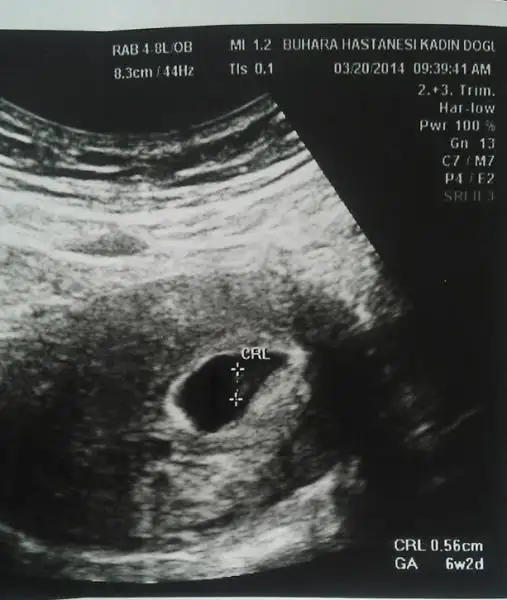

Hoşgeldin arkadaşım darısı başımıza artıkben de aranızdayım artıkdün kalp atışlarını da gördüm bebeğimin

ben de aranızdayım artıkdün kalp atışlarını da gördüm bebeğimin

bende 6+3 günlük hamileyimkese geçen hafta görüntü kalp atışları için cts günü kontrolümüz var. fakat kaygılarım o kadar çok ki bir türlü kurtulamıyorum ya kalp atışları duyulmaz ise ya bi şey olur ise diye kendi kendimi yiyip duruyorum benim gibi olan var mı acaba ??

Rabbime bin şükürler olsun Allah'ımmm nasıl güzel bir duyguymuş o pıt pıtlar.. Minnacık bir varlığın kalbinin sesi kendinden ne kadar büyük de çıkıyor ne mucize Rabbim güm güm güm güm... Hastaneden geldiğimden beri ağlıyorum öyle güzel bir duyguymuş ki.. Rabbim duymayanlara hayırlısıyla duymayı nasip etsin inşallah.. Duyanlara da sağ salim kucaklarımıza almamızı nasip etsin.. Şükür ki ilk gebeliğimdeki gibi olmadı o güm güm'ü duydum mercimeğimin ya kurban olurum onu yaradana..

Eki Görüntüle 1029642